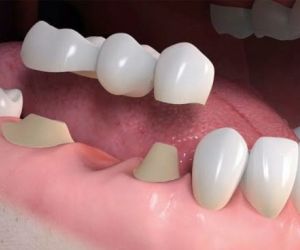

A indicação da extração de dente é uma notícia desagradável para a maioria das pessoas. Podemos afirmar que grande parte dos profissionais dentistas sempre trabalha para preservar ao máximo um dente, e, portanto, a indicação da extração dentária normalmente só ocorre quando o dentista identifica qu…